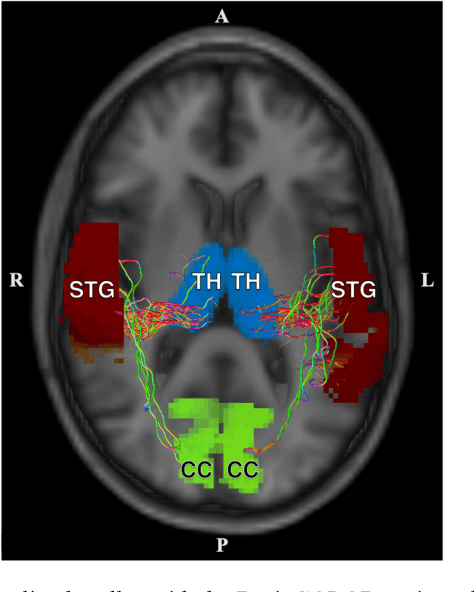

Abstract:Veterans with mild traumatic brain injury (mTBI) have reported auditory and visual dysfunction that persists beyond the acute incident. The etiology behind these symptoms is difficult to characterize with current clinical imaging. These functional deficits may be caused by shear injury or micro-bleeds, which can be detected with special imaging modalities. We explore these hypotheses in a pilot study of multi-parametric MRI. We extract over 1,000 imaging and clinical metrics and project them to a low-dimensional space, where we can discriminate between healthy controls and patients with mTBI. We also show correlations between the metric representations and patient symptoms.